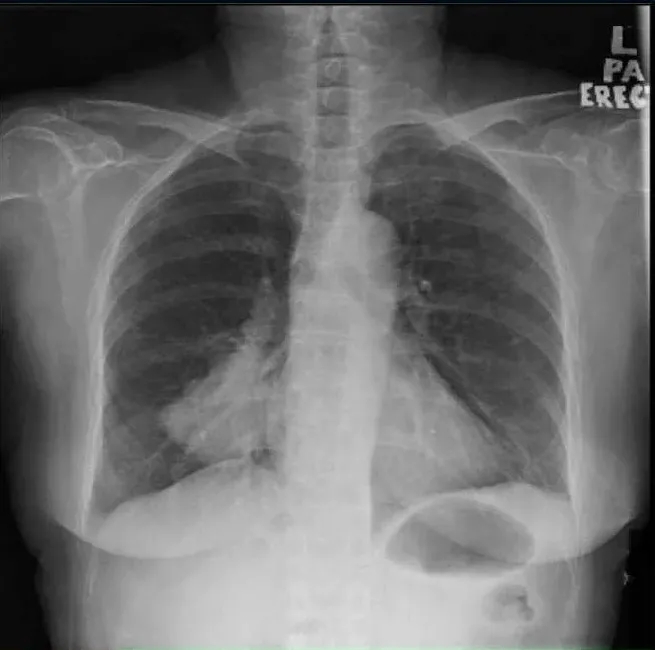

她第一次就诊时的常规胸片(图1)检查偶然发现了右肺肿块。随后的胸部增强计算机断层扫描(CT)(图2)显示肺右下叶后基底段的肺肿块大小为4.7×7.0×7.0 cm(前后×宽度×头尾)。肿块附近也有卫星结节。对肿瘤进行支气管镜活检,组织病理学检查(HPE)结果显示腺癌,证实为原发性肺恶性肿瘤,表皮生长因子受体(EGFR)基因的外显子19缺失。

图1. 胸部X线,右下肺叶有肿块

图2. 胸部计算机断层扫描显示右下叶肿块,周围有卫星结节(箭头)